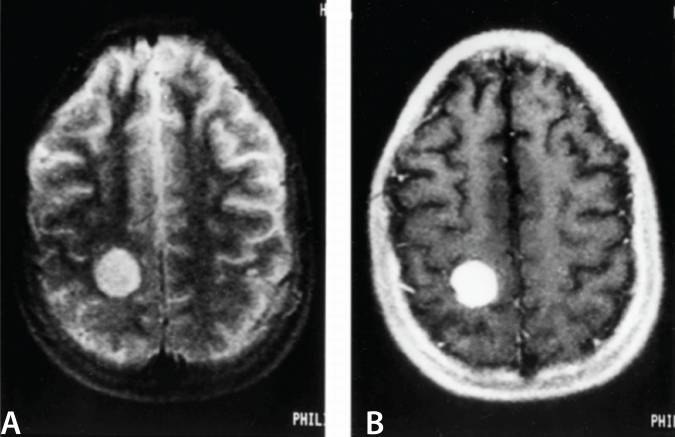

• Angiosarcoma

Angiosarcoma. MRI of the brain of a patient diagnosed with primary cardiac angiosarcoma which had metastasized to the brain. Image taken at the Department of Cardiovascular Surgery, Kartal Kosuyolu Heart Research and Training Hospital, Istanbul, Turkey and published under the Creative Commons Attribution License in September-October 2018. Arzu Antal Donmez, Davut Cekmecelioglu, Taylan Adademir, Ekrem Yilmaz, and Hizir Mete Alp. Not altered. CC BY 4.0